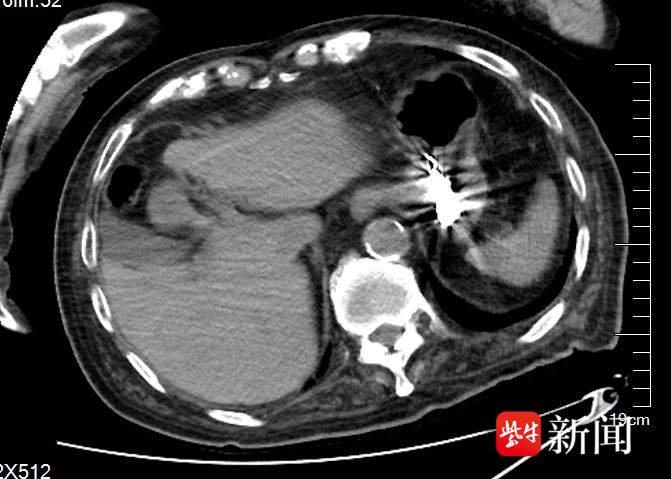

- 需透過影像學檢查(如X光、電腦斷層)確認假牙位置與是否造成損傷。